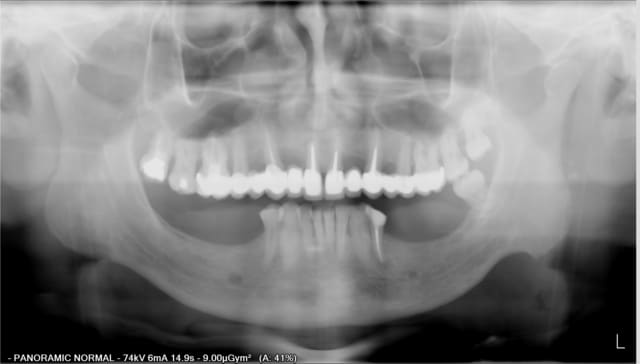

j'ai besoin de vos regards expérimentés pour savoir si je suis dans les clous avec le plan de traitement que j'envisage pour ce patient:

homme, 61 ans, ancien fumeur (arrêt depuis 5 ans), pas de pb général, légère classe II, brossage correct sans plus.

Il veut du fixe en bas.

34 a été retraitée: silence clinique depuis (env 6 mois) mais image toujours présente confirmer par le scan.

le volume osseux me permet d'envisager:

en 45 : 3,7/8 en mésial du foramen

en 46 :3.7/8

en 46/47: 3.7/8

en 34 : 3,7/12

en 35 : 3,7/8

en 36 : 4.8/6

n'ayant pas ou très peu d'expérience sur des bridges post avec des implants aussi courts et étroits, que me conseillez vous:

3implants par secteur, uniquement 2 par secteur, ou au contraire augmentation osseuse pour poser plus long et plus gros.